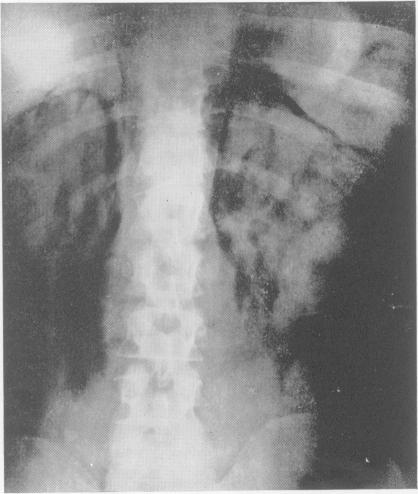

Radiology in the investigation and management of hypertension.

Postgrad Med J. 1958 Oct;34(396):514-23 passim. doi: 10.1136/pgmj.34.396.514.